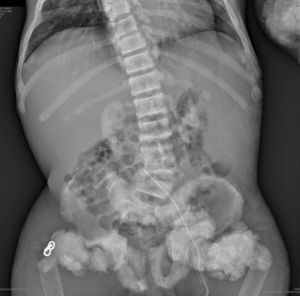

En la radiografía de tórax (fig. 1) se observaron calcificaciones periarticulares en los hombros de aspecto nodular, osteoesclerosis vertebral y colapsos vertebrales dorsales 5 y 6, secuelas de fracturas costales y fractura del húmero derecho. En la radiografía de abdomen (fig. 2) se apreciaron nefrocalcinosis bilateral, osteoesclerosis vertebral y en huesos de la pelvis, calcificaciones periarticulares de aspecto nodular y fractura subtrocantérica bilateral.

Nefrocalcinosis bilateral, osteoesclerosis vertebral (columna en jersey de rugby) y osteosclerosis Paget-like en huesos de la pelvis. Datos de osteomalacia. Calcificaciones periarticulares de aspecto nodular. Fractura subtrocantérica bilateral. Material quirúrgico en el extremo proximal del fémur derecho.